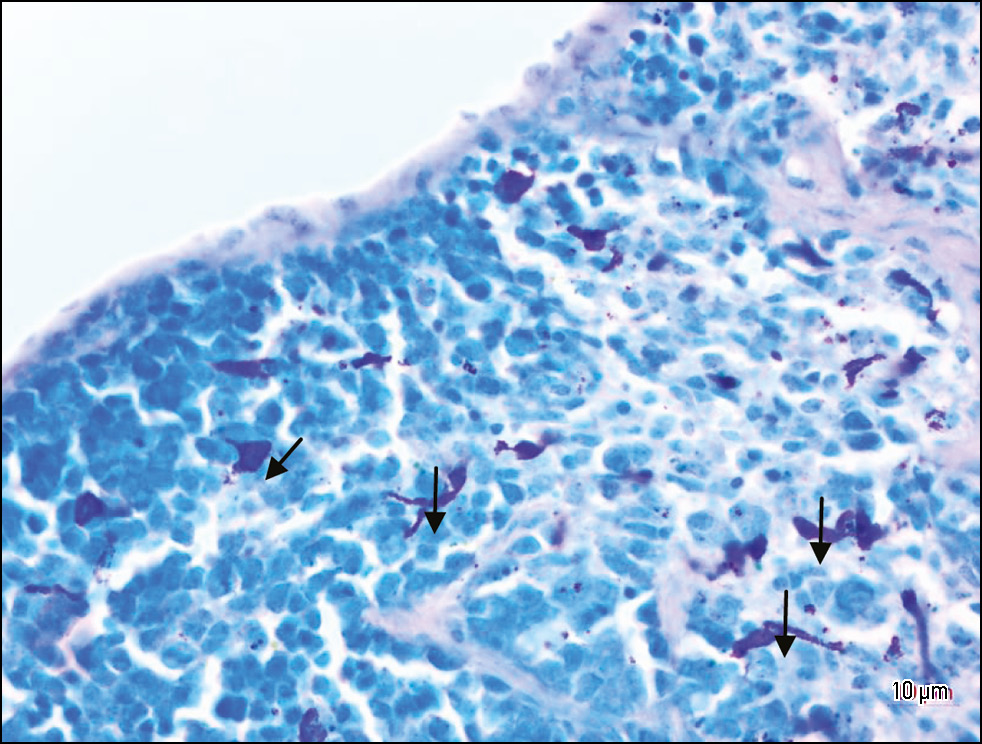

METHODS: An experimental, single-center, prospective, controlled study was conducted. Spleen samples from laboratory mice (n = 23) were assessed. The population of mast cells was quantitatively assessed on histological sections of the spleen. The mice were divided into 5 groups: Group 1 included intact animals (n = 3); Group 2 included irradiated animals with a total absorbed dose of 7 Gy (n = 5); Group 3 included irradiated animals with a total absorbed dose of 7 Gy who received oral soluble beta-D-glucan 15 minutes before irradiation (n = 5); Group 4 included irradiated animals with a total absorbed dose of 18 Gy (n = 5); Group 5 included irradiated animals with a total absorbed dose of 18 Gy who received oral soluble beta-D-glucan 15 minutes before irradiation (n = 5). Samples were collected on days 14 and 30 after the start of experimental exposure. Samples were fixed in 10% buffered formalin, dehydrated in alcohol, and embedded in paraffin. The Romanowsky–Giemsa staining was used. The structure and number of mast cells were assessed on each histological slide. Statistical analysis of the findings was performed.

RESULTS: The density of mast cells in the spleen of laboratory mice at an absorbed dose of 7 Gy changed insignificantly compared to the intact group. At a total absorbed dose of 18 Gy, there was a significant increase in the density and functional activity of mast cells. Beta-D-glucan administration before irradiation at a total absorbed dose of 7 Gy and 18 Gy reduced the number of mast cells by 2.5 times and 1.25 times, respectively, compared to irradiated animals without beta-D-glucan administration (Group 4).

CONCLUSION: The density of mast cells in the spleen depends on the absorbed dose of X-ray irradiation. Beta-D-glucan administration 15 minutes before exposure reduces the density of mast cells, which can be considered a positive radioprotective effect.